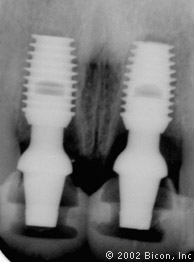

Дооперационная рентгенограмма

Установка двух 5.0mm x 8.0mm HA имплантантов Bicon

Определение направления оси и глубины шахты имплантантов